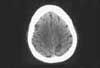

Figure 1

CNs were intact, with no facial asymmetry and normal CN V function. Motor testing revealed no drift. Deep tendon reflexes were 2/2 and symmetric; Babinski reflex was negative. On sensory testing, the patient distinguished sharp from dull on the left upper extremity but exhibited extinction on simultaneous testing. On further testing, she demonstrated astereognosis when asked to identify a quarter placed in her left palm. A noncontrast head CT scan revealed a right parietal cortex infarct (Figure).

Commentary. This case demonstrates the importance of pursuing the clinical evaluation of a patient with a neurologic complaint. The patient had a sensory deficit that was not evident during the initial examination; a more in-depth evaluation uncovered it.

Making the final diagnosis of a cortical stroke was the key to proper management of this patient. Because patients who have had one stroke are at increased risk for another, it is necessary to search for reversible causes of thromboembolism. These patients require a careful evaluation that includes an ECG, an echocardiogram, carotid artery imaging, and a complete hematologic assessment.7